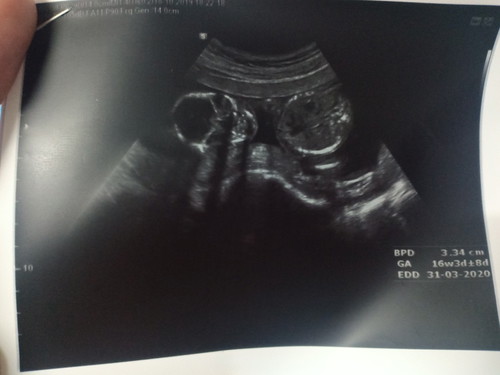

ท่าลูกตอนตั้งครรภ์

อยากทราบว่า ถ้าผลซาวออกมาแบบนี้ ปกติมั้ยคะ มีใครเคยซาวแล้วลูกอยู่ท่านี้บ้าง ( ท้องแรกค่ะเลยแอบกังวล เพราะตัวเองอยากเห็นแขนขาลูก แต่คุณหมอบอกว่าปกติ )